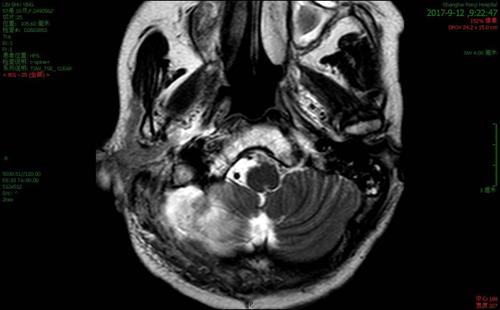

鼻咽部增强磁共振检查结果显示:鼻咽癌伴淋巴结转移;鼻内镜下鼻咽部

手术后复查增强核磁共振,肿瘤完全切除(图10,图11,图12).

患者脑磁共振图象及相关实验室检查,腰穿结果公布如下